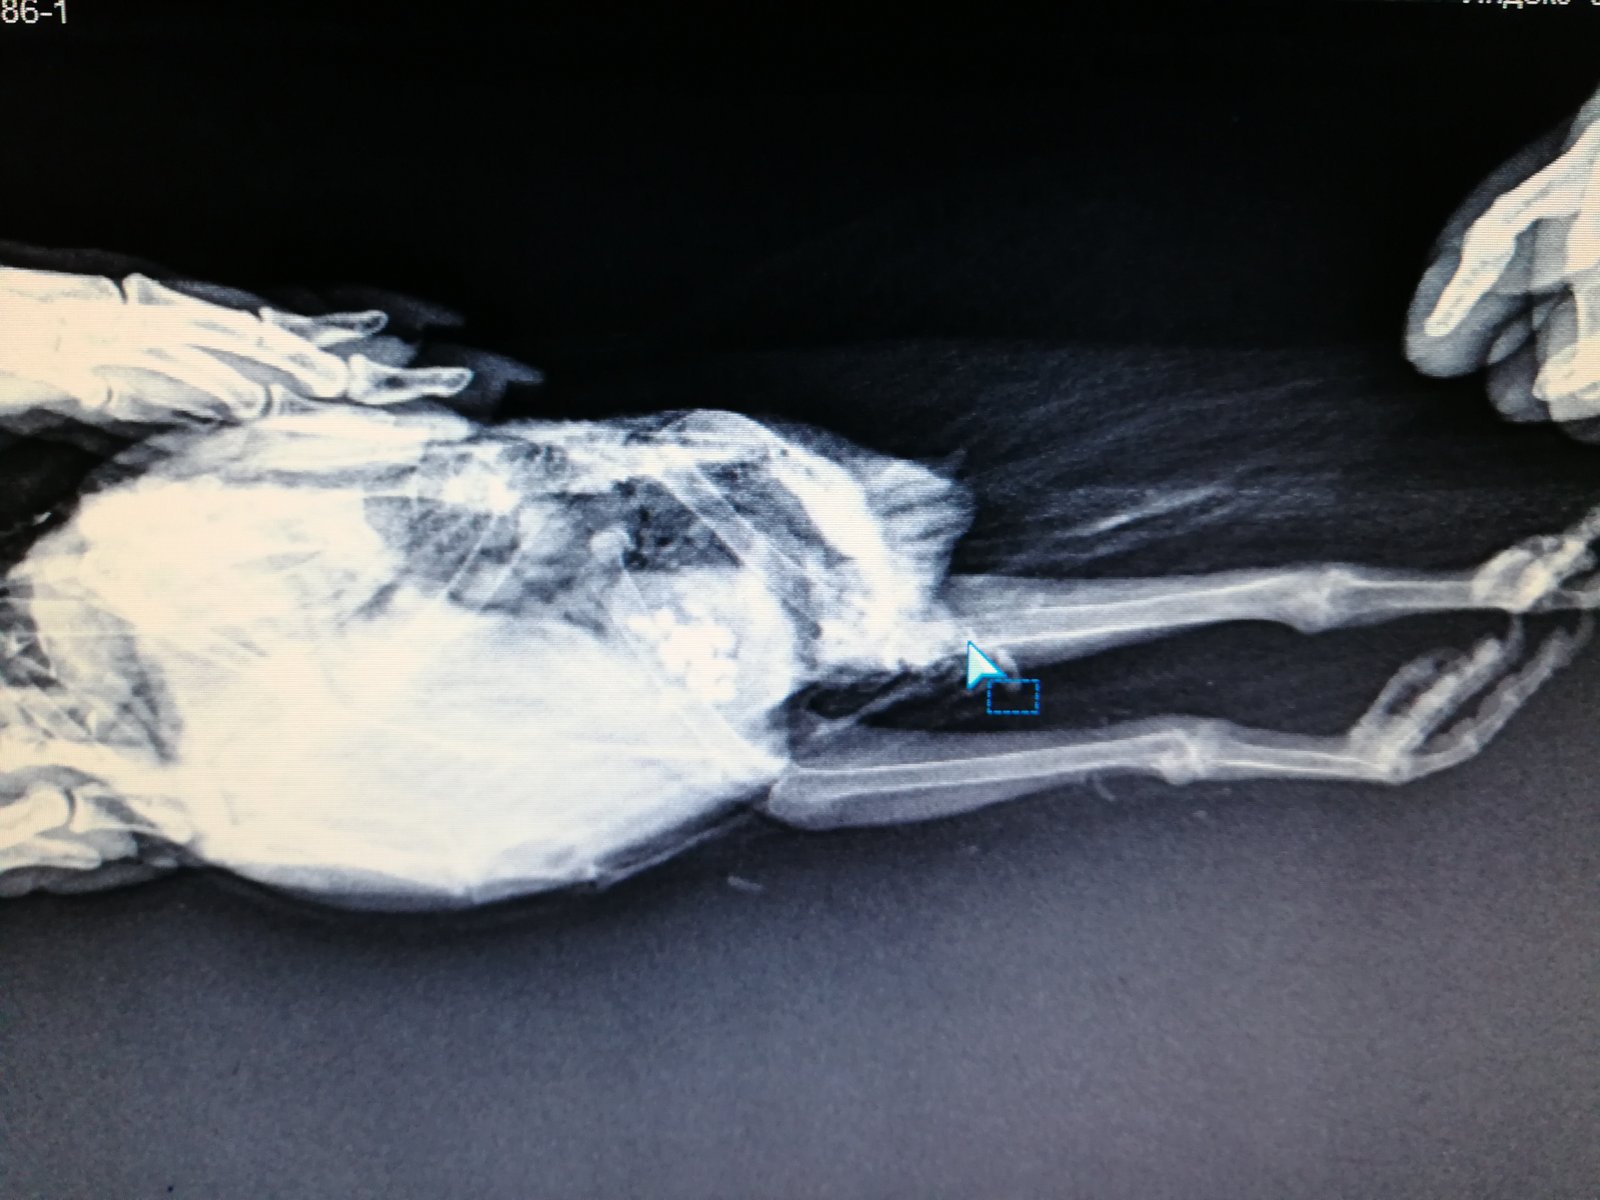

Elena1811 Опубликовано 7 марта, 2020 Автор #113 Опубликовано 7 марта, 2020 Мы старались как могли. Не получается его развернуть полностью из-за левого крыла. Не разворачивается доконца. Боялись сломать

Zosia Опубликовано 7 марта, 2020 #124 Опубликовано 7 марта, 2020 Если есть файлы на флешке- то мне на почту киньте. Т.к. в переснятом виде снимки нечитабельны. zofia68@mail.ru

Elena1811 Опубликовано 11 марта, 2020 Автор #130 Опубликовано 11 марта, 2020 Получила ответ от Зофии. Нужны разъяснения. И некоторые препараты я не могу купить Вот что пишет Зофия: Ну, отличить голубя от голубки я по фото не смогу. Хотя ИМЪО мне видится голубка. И те новообразования в брюшной полости (которые могцт передавливать нервные окончания, идущие к лапкам)- характерны именно для голубок, у меня даже фото есть гранулем, которые у них «рождаются» вместо яиц. Так что ИМХО- итраконазол в дозе 15 мг/кг каждые 12 чсов, нисиатин в дозе 75 000 ед в сутки на 100 гр веса, преднизолон из арсчета 3 мг/кг в сутки. Первый курс- 21 день. Для прикрытия преднизолона- Деринат капли назальные, принимать орально 4 капли в сутки весь курс. Обязательно гепатовте- 0,2-0,3 мл в сутки. По крылу- ваш снимок не дает возможности оценить фатальность нарушений. Но скорее всего- там уже вряд ли что можно сделать (и по-любому это вопрос-не вопрос жизни). ......... У нас беда с преобретением лекарств, рецепты только лишь на аналгин не нужны..